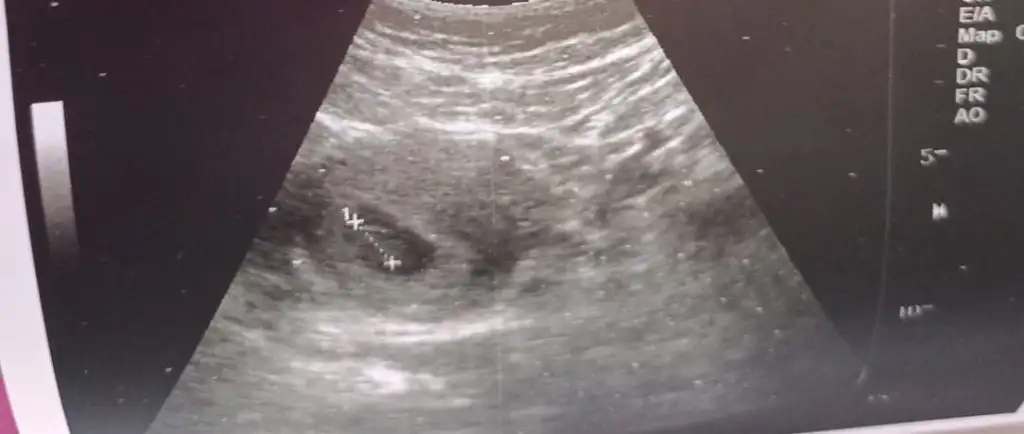

Arkadaşımın da ultrason fotosunu atmıştım ona da yorum yapar mısınız? 12 haftalık karından.

11+6 günlük karından bakıldı